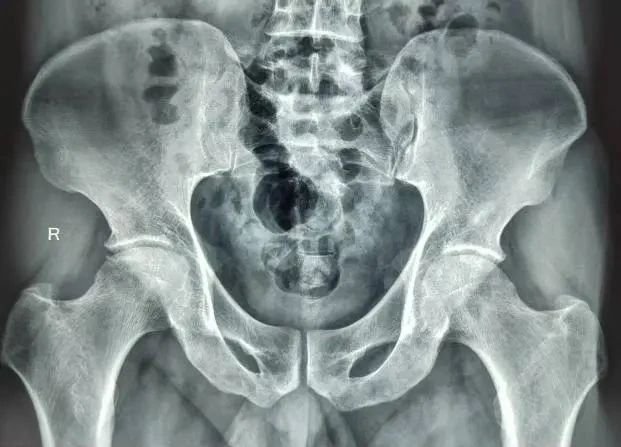

术后X光片